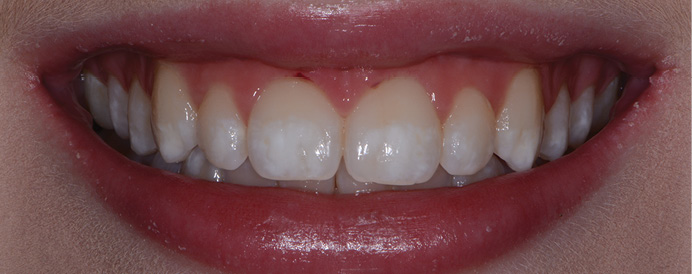

Figures 1 and 2: The restorations on the molars are Class 5 zirconia colored in the presintered stage, nonglazed or superficially stained. They are polished only. The restorations cannot be differentiated from the lithium disilicate restorations on the remainder of the teeth and implants. Note the lack of simulated caries on the occlusal surfaces, which is discouraged. Natural teeth without caries do not have occlusal color. Technicians: Jed and John Archibald; Archibald Associates; Orem, Utah. Clinician: Gordon Christensen, DDS, prosthodontist.